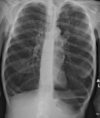

Estudios de imagen en COVID-19

Rx útil en seguimiento, poco sensible al inicio * Hallazgos similares a cualquier neumonía viral * Consolidación en vidrio despulido *Patrón reticular TC mayor sensibilidad + Consolidación periféricas en vidrio esmerilado

COVID-19 con patrón de vidrios despulido

COVID-19 con patrón en vidrio despulido